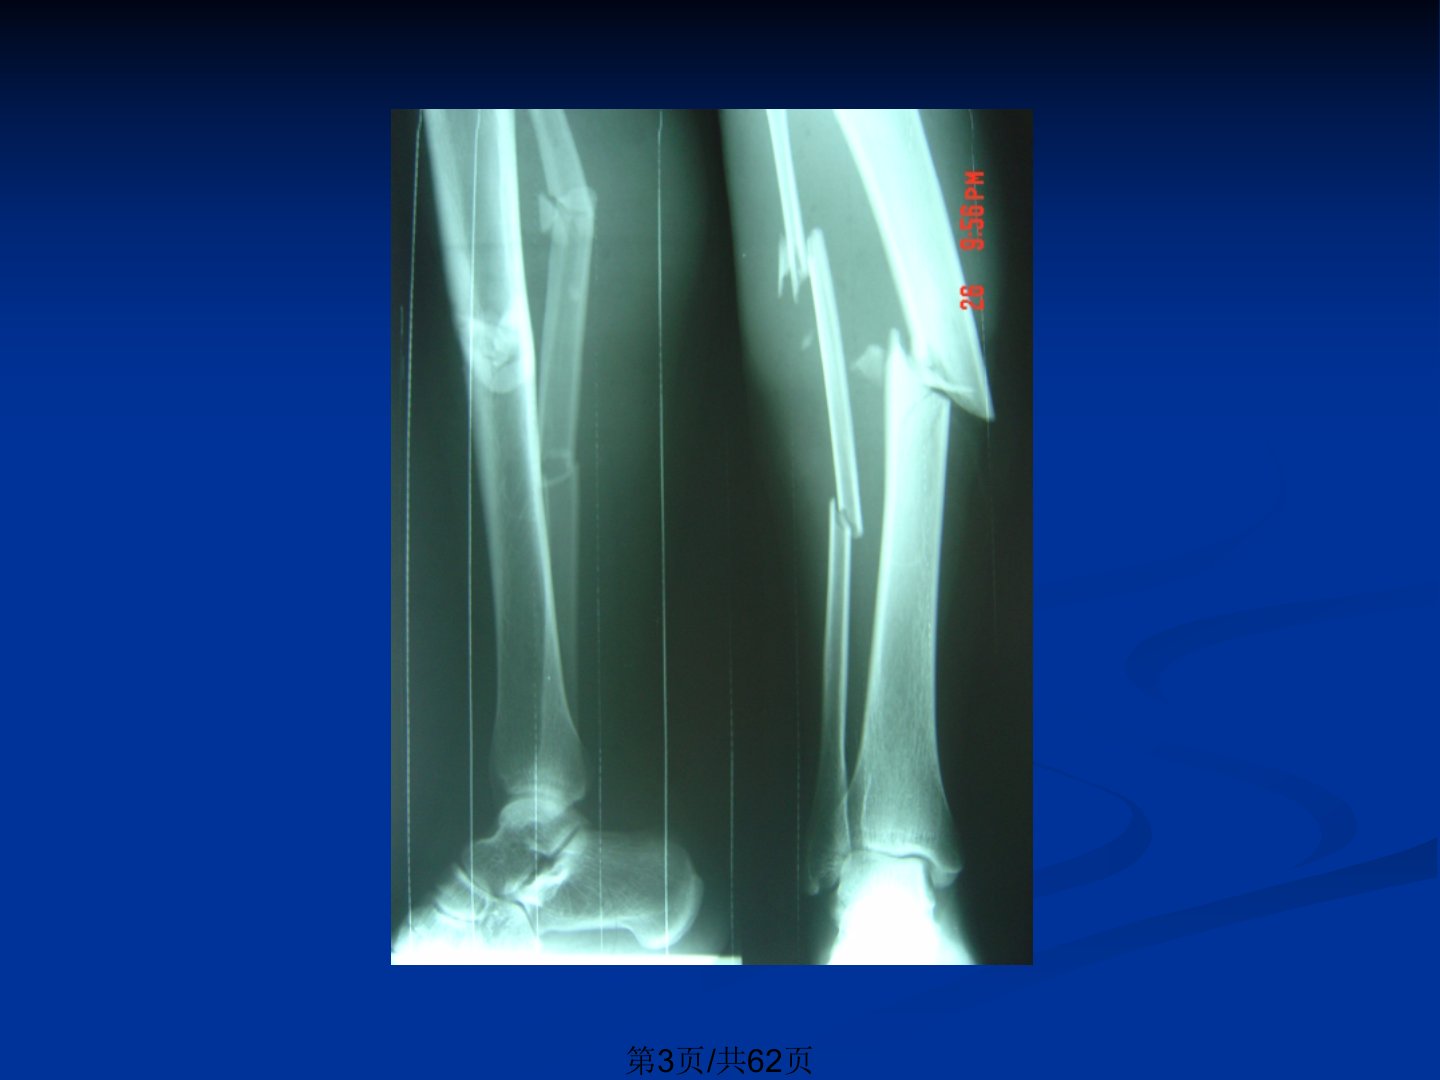

本文是骨科常见疾病概览主要涵盖骨折、关节脱位、脊柱脊髓损伤及骨盆骨折等关键疾病。骨折定义为骨的完整性或连续性中断原因包括直接暴力、间接暴力、肌肉拉力、积累劳损及骨病。骨折分为开放性与闭合性、不全性与完全性移位形式包括成角、短缩等。临床表现含局部畸形、反常活动等专有体征及疼痛、肿胀等全身症状。并发症分早期与晚期局部合并症有大出血、脊髓神经损伤等晚期则包括骨折延迟愈合、关节功能障碍等。治疗原则为复位、固定与功能锻炼复位包括手法与切开复位两种。关节脱位指关节面失去正常对合关系治疗以手法复位为主时间越早越好。脊柱脊髓损伤需根据损伤机制、暴力方向及部位分类治疗原则为矫正畸形、解除压迫及稳定脊柱。骨盆骨折多由暴力引起常合并全身多发损伤治疗需根据骨折类型选择。此外还介绍了化脓性骨髓炎其致病菌多为金葡菌等治疗强调早诊断、早治疗。